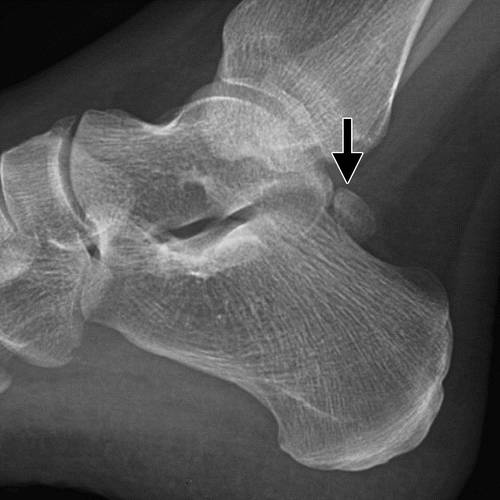

根据Hawkins标准,横突骨折最常分为三种类型:简单(I型),粉碎型(II型)和切片(III型)(图15)(33)。 类型I,最常见的,由具有从踝关节表面延伸到距下关节的单个断裂线的大片段组成(图16)。 类型II是涉及整个侧向过程和两个关节表面的粉碎性骨折(图17)。 III型骨折发生在窦性the骨区域,并且通常仅在横向X线照片上可视化。

图16 Hawkins I型距骨横突骨折。 (a)踝的横向放射线照片显示横突的非位移断裂(箭头)。 (b)踝的AP射线照片显示横突的非位移断裂(箭头)。 在这个视图上可以看到踝关节表面的参与。 (c)踝的矢状的CT图像显示了简单的非置换横突骨折(箭头)。

图17a Hawkins II型距骨横突骨折。 (a)踝的AP射线照片显示横突的断裂(箭头)。 (b)冠状重建的踝关节的CT图像显示了涉及整个横突(箭头)的粉碎性骨折。